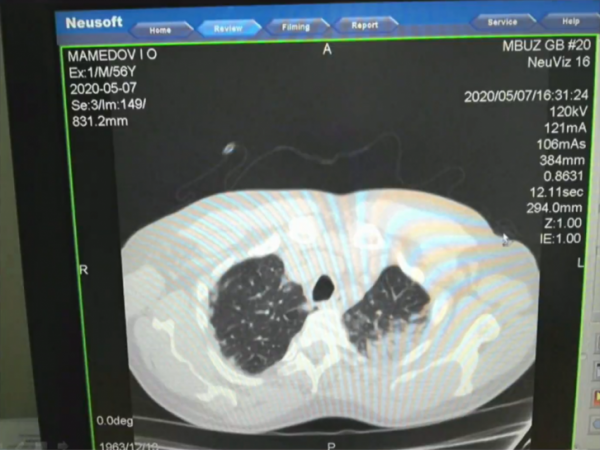

Глава Минздрава Ростовской области Татьяна Быковская во время заседания оперштаба показала снимки органов легких у людей с подтвержденным коронавирусом. На слайдах видно, как инфекция поражает легочную ткань, оставляя матовые помутнения.

— Всё, что темное, — это ткань легкого, а светлое — так называемое матовое стекло. Это показатель того, что наступает необратимый процесс. Легкие наполняются кровью, и дышать пациент самостоятельно не может, — объяснила Быковская.

Из-за того, что такие поражения легких на снимках выглядят помутневшими, врачи и ученые называют его «эффектом матового стекла». Оно проявляется даже у тех, кто переболел коронавирусом без симптомов. Ранее ученые выяснили, что примерно две трети заболевших переносят коронавирус без видимых симптомов. При этом у половины из них есть пневмония, которую пациенты не могут заметить самостоятельно.

Темное — это ткань легкого, светлые пятна — поражения

Фото: оперштаб по коронавирусу Ростовской области